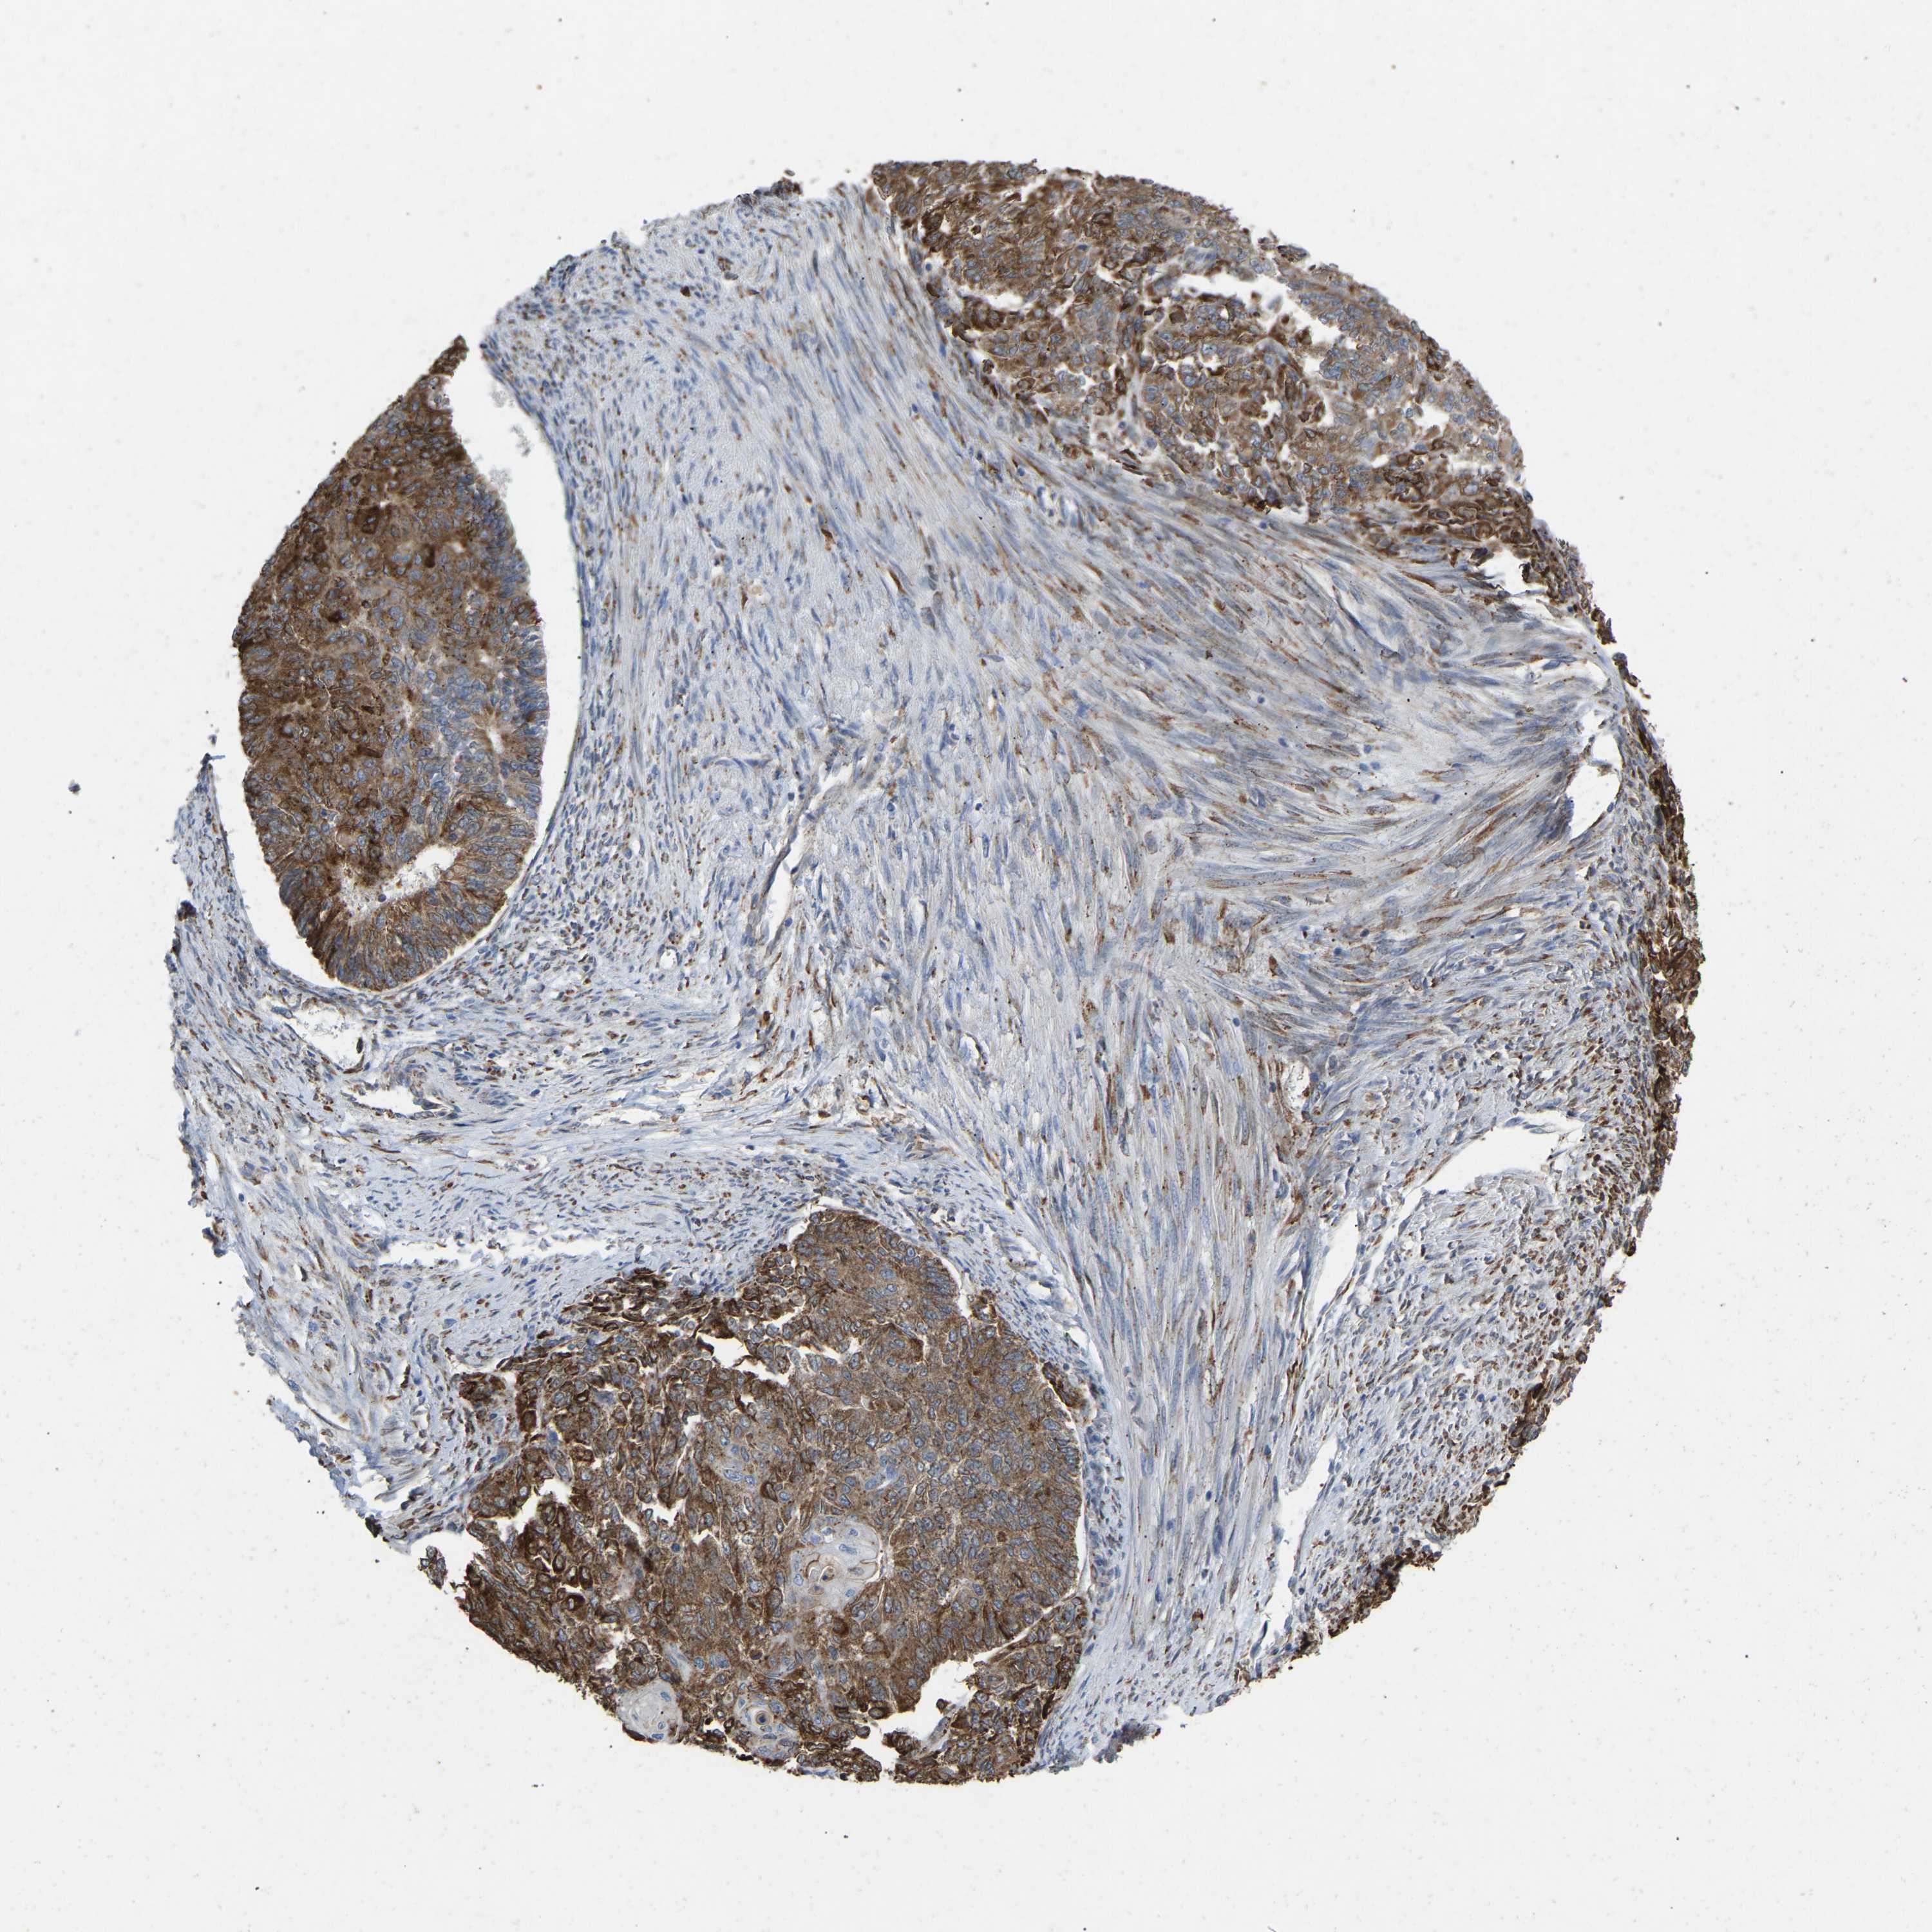

ENDOMETRIAL CANCER - Protein expressioni

A mouse-over function shows sample information and annotation data. Click on an image to view it in a full screen mode. Samples can be filtered based on level of antibody staining by selecting one or several of the following categories: high, medium, low and not detected. The assay and annotation is described here.

Note that samples used for immunohistochemistry by the Human Protein Atlas do not correspond to samples in the TCGA dataset.

Antibody stainingi

Antibody staining in the annotated cell types in the current human tissue is reported as not detected, low, medium, or high, based on conventional immunohistochemistry profiling in selected tissues. This score is based on the combination of the staining intensity and fraction of stained cells.

Each image is clickable and will lead to virtual microscopy that enables deeper exploration of all samples and also displays staining intensity scores, fraction scores and subcellular localization as well as patient and tissue information for each sample.

Antibody CAB019436

Staining

High

Medium

Low

Not detected

Intensity

Strong

Moderate

Weak

Negative

Quantity

>75%

75%-25%

<25%

None

Location

Nuclear

Cytoplasmic/membranous

Cytoplasmic/membranous,nuclear

Adenocarcinoma, NOS